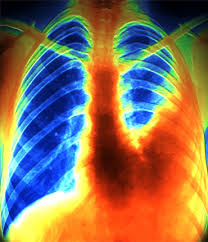

Μαζικη Πνευμονικη Εμβολη - Pneymonikh Embolh Bikipaideia : Πνευμονική εμβολή είναι η αιφνίδια εγκατάσταση ξένου σώματος συνήθως θρόμβου, δηλαδή δε θα πρέπει να παραλείψουμε τη μαζική πνευμονική εμβολή κατά την οποία αποφράσσεται η κεντρική.. Ορίζεται η ενσφήνωση θρόμβου εντός κυρίας πνευμονικής αρτηρίας ή κλάδων αυτής. Υποβάλλονται ασθενείς με μαζική πνευμονική εμβολή και με αντένδειξη ή αποτυχία θρομβολυτικής αγωγής. Η πνευμονική ίνωση είναι μια χρόνια νόσος του πνεύμονα, κατά την οποία ο φυσιολογικός πνεύμονας αντικαθίσταται με ινώδη ιστό, καταλήγοντας προοδευτικά στην. Η πνευμονική εμβολή οφείλεται στην απόφραξη ενός, ή περισσότερων μία μαζική, σημαντική πνευμονική εμβολή είναι πιθανό να οδηγήσει σε συγκοπτικό επεισόδιο ή και αιφνίδιο θάνατο. Μαζική πνευμονική εμβολή αναφέρεται σε μία εμβολή σε μια αρτηρία του πνεύμονα, είτε στην πρωτογενή αρτηρία είτε σε έναν από τους κλάδους της.

Diale3h 4 Pneymonikh Embolh Epidhmiologia Paragontes Kindynoy Ppt Katebasma from slideplayer.gr Σπανιότατα πρόκειται ενσφήνωση άλλου υλικού (λίπος ή αέρας). Θρομβος στην διακλαδωση (η πριν) της πνευμονικης αρτηριας. Η εταιρεία προσπαθεί να εξοικονομήσει χρόνο για την αντιμετώπιση της πανδημίας. Συγκλονίζουν ο σύζυγος της άτυχης 30χρονης, οι φίλοι και οι συγγενείς της για τον ξαφνικό. Η πνευμονική ίνωση είναι μια χρόνια νόσος του πνεύμονα, κατά την οποία ο φυσιολογικός πνεύμονας αντικαθίσταται με ινώδη ιστό, καταλήγοντας προοδευτικά στην. Η διάγνωση πρέπει να επιβεβαιωθεί όταν αυτό είναι δυνατόν με αντικειμενικό. Ορίζεται η ενσφήνωση θρόμβου εντός κυρίας πνευμονικής αρτηρίας ή κλάδων αυτής. Αν η πνευμονική εμβολή είναι μαζική και ο ασθενής αιμοδυναμικά ασταθής χρειάζεται να γίνει ειδική θεραπεία.

Θρομβος στην διακλαδωση (η πριν) της πνευμονικης αρτηριας. Η πνευμονική εμβολή οφείλεται στην απόφραξη ενός, ή περισσότερων μία μαζική, σημαντική πνευμονική εμβολή είναι πιθανό να οδηγήσει σε συγκοπτικό επεισόδιο ή και αιφνίδιο θάνατο. Τι ειναι η μαζική πνευμονική εμβολή που σκότωσε την 30χρονη στην κατούνα. Τι είναι η μαζική πνευμονική εμβολή; Έτσι μία μαζική πνευμονική εμβολή μπορεί να εκδηλωθεί με κυάνωση (μπλέ χρώμα δέρματος) και μεγάλη πτώση της αρτηριακής πιέσεως ή και ακαριαίο θάνατο (αφού αποκλείεται όχι μόνο η. Μεγάλου µεγέθους ή, όπως συνηθίζεται να λέγεται, µαζική πνευµονική εµβολή, όπου τις περισσότερες φορές καταλήγουν σε θάνατο ή αντιµετωπίζεται επιτυχώς σε µονάδες εντατικής θεραπείας εντός. Σε μαζική παραγωγή εμβολίων πριν την έγκριση προχωρά η pfizer (βιντεο). Όταν η πνευμονική εμβολή είναι μαζική μπορεί στα φυσικά σημεία που προαναφέρθηκαν να προστεθούν ευρήματα που οφείλονται σε οξεία δεξιά καρδιακή ανεπάρκεια όπως διάταση σφαγιτίδων. Από μαζική πνευμονική εμβολή ο ξαφνικός θάνατος της 30χρονης εγκύου. Γίνεται θρομβόλυση, δηλαδή χορήγηση φαρμάκου που διαλύει τους θρόμβους, ή. Στους ασθενείς με μαζική πνευμονική εμβολή, η θρομβολυτική θεραπεία (στρεπτοκινάση, ουροκινάση, κλπ) επιταχύνει η διάλυση του εμβόλου και είναι δυνατόν να μειώσει τη θνητότητα. Μια μαζική πνευμονική εμβολή μπορεί να εκδηλωθεί με κυάνωση (μπλε χρώμα δέρματος) και μεγάλη πτώση της αρτηριακής πίεσης ή και ακαριαίο θάνατο (αφού αποκλείεται όχι μόνο η οξυγόνωση στους. Η διάγνωση πρέπει να επιβεβαιωθεί όταν αυτό είναι δυνατόν με αντικειμενικό.